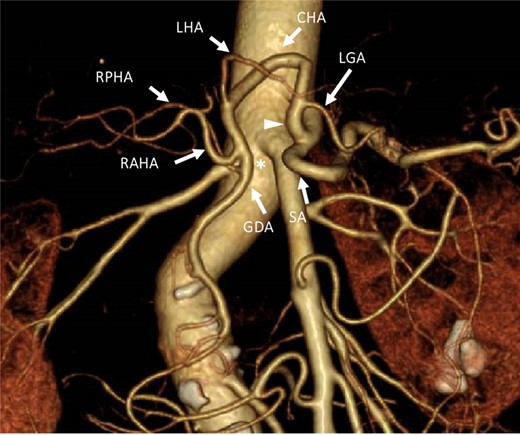

Three-dimensional computed tomography angiographic image from an anteroposterior view. The celiac artery branched into the SA. A common trunk (white arrowhead) branched into the LGA and the common hepatic artery, which arched toward the cranial side. No arterial bridge existed between the celiac trunk and the GDA (asterisk). LGA: left gastric artery. CHA: common hepatic artery. SA: splenic artery. LHA: left hepatic artery. RAHA: right anterior hepatic artery. RPHA: right posterior hepatic artery. GDA: gastroduodenal artery.